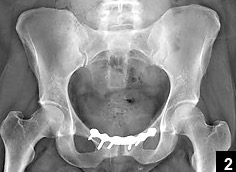

Flyers defenseman Mark Streit will have surgery on Tuesday morning to repair a pubic plate detachment. The surgery will be performed by Dr. William Meyers. He is expected to be out for six weeks.

OH COME ON! What does that even mean?! If I tore my pubic plate, I’d retire. Not if I was a hockey player, but now. If I tore my pubic plate, I’d retire from blogging. What’s the sense in continuing on with a torn pubic plate? Tap out. I Googled it and, uh, DON’T DO THAT:

Voila_Capture 2015-11-14_04-05-47_PM

OWWWW. OWWWWWW. OWWWWWWW!